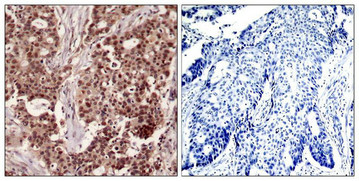

Immunohistochemical analysis of paraffin-embedded human breast carcinoma tissue using NFkB-p105(Phospho-Ser927) Antibody(left) or the same antibody preincubated with blocking peptide(right).